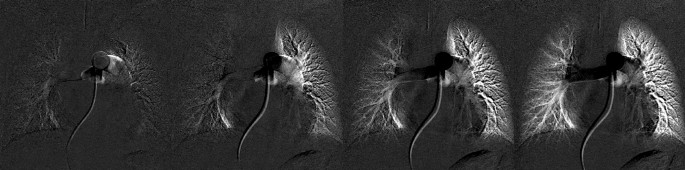

An example of TIC for patient D is shown in Fig. 7 (Supplementary Table S1), and its corresponding image is shown in Fig. 8. The horizontal axis corresponds to the frame number, where frame #1 is the first frame after contrast injection. In this case, the starting times of the blood flow to the right and left lung regions were slightly different. The difference can be observed in the figure; the slope of the TIC of the right region is slightly shifted to the right compared to the left region. Using TIC combining both the right and left regions (R + L), a representative six-frame time window (frame 21–26) was detected where the maximum slope is observed, as shown with triangle marks. The time window is extended by six frames to 14 frames by including four additional frames in each side of the selected representative time window. In the selected 14 frame candidate time window (frames 17–30), each six frames that show maximum slopes of each right and left TIC are selected independently (frames 21–26 for the left region that are marked as filled circles and frames 24–29 for the right region that are marked as filled rectangles). The slope for the right region is 0.009824, and the slope for the left region is 0.014666. The right to left region was calculated as 40:60.

Example of a time-signal intensity curve. Blue represents the right lung region, green represents the left lung region, and black represents the mean of the right and left regions (R + L). The triangle mark is the representative time window using the R + L curve. Transparent circle and rectangle marks are candidate points. Filled circle and rectangle marks are the final optimized points.

Corresponding image of Fig. 7, frame 22, 25, 28, and 31. For better visualization, frame 21 was subtracted from all the other frames. The starting time of blood flow supply was slightly different between the right and left lung regions.